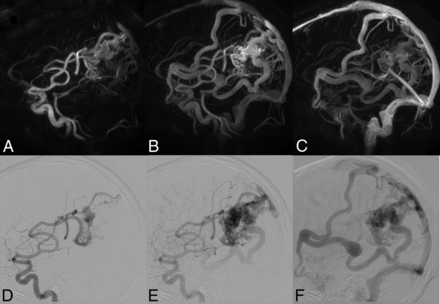

The same patient as shown in Fig 3. Top row: HYPRFlow images in the sagittal plane: arterial (A), mixed (B), and venous phase (C). Bottom row: corresponding DSA images: arterial (D), mixed (E), and venous phase (F). Note the excellent correlation of the arterial supply and venous drainage pattern.

When we compared M2/M3 arterial branches, there was no significant difference between the mean image quality scores of HYPRFlow (3.18) and TOF (3.26) (P > .05), but there were very significant differences between the image quality of both HYPRFlow and TOF compared with DSA (3.94) with P < .002 and .004, respectively. DSA deep and superficial venous image quality (3.82) was significantly better than HYPRFlow (3.08) (P < .005) (Figs 2⇓–4).

The Spetzler-Martin grades and number of patients in each category based on DSA were grade I (n = 2), grade II (n = 4), grade III (n = 3), grade IV (n = 3), and grade V (n = 2) (Figs 2⇑–4). There was 1 instance in which very small deep medullary draining veins were not identified on the HYPRFlow examination, resulting in disagreement with the DSA Spetzler-Martin grade (Fig 5); otherwise HYPRFlow and DSA were in concordance.